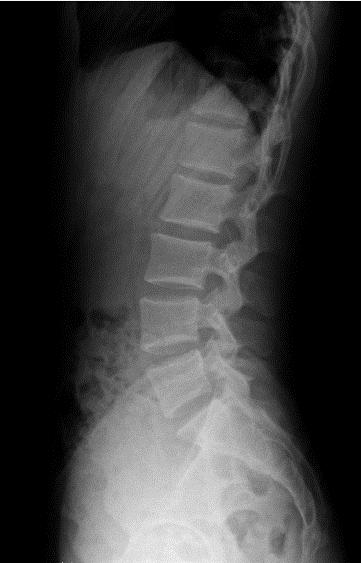

全自动全景成像(选配)

三次点击,两个步骤,一气呵成

全过程一分钟内完成,摄影条件智能设定,根据不同体厚智能曝光补偿,宽幅窄缝按需选择,无需往返机房调整机架位置,一气呵成自动全景成像